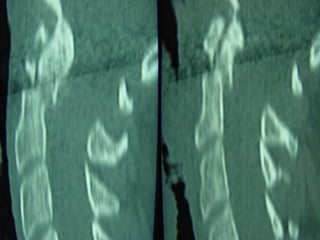

CCTT -- ssccaann

–PPoosstteerriioorr aarrcchh

wweellll ddeeffiinneedd

–RReettrrooppuullsseedd

ffrraaggnneennttss

ccoorrdd -- nneerrvveess

ccoommpprroommiisseedd

–AAddjjaacceenntt lleevveell

iinnjjuurryy –– 1100%%

CCTT ssccaannss ggoooodd ffoorr

vviissuuaalliizziinngg

ffrraaccttuurreess bbuutt ddooeess

nnoott pprreeddiicctt

iinnssttaabbiilliittyy